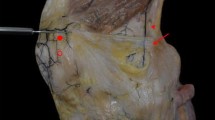

Medial aspect of a right knee in extension. The superficial medial collateral ligament (sMCL) has been elevated from distal (at the bottom of the picture) to proximal to display the deep medial collateral ligament (dMCL). The joint capsule has been split alongside the edges of the dMCL, revealing the femoral condyle. The lines across the femoral attachments of the ligaments show their A-P widths. The midpoint of the attachment of the dMCL is distal and posterior to the midpoint of the attachment of the sMCL. The fibres of the dMCL fan out distally and anteriorly to give a wide tibial attachment, making it ideally aligned to counter tibial external rotation

The fibres of the dMCL fan out to a 22 mm mean wide tibial attachment, spreading from 33 to 76% posterior from the anterior edge of the medial plateau, (Figs. 7, 9; Table 2), and was 8 mm mean (15%) distal to the plateau. The dMCL fibres were aligned antero-distally from the femur to the tibia, so it is well aligned to resist tibial external rotation (Fig. 10).

a Medial aspect of a right knee. The superficial medial collateral ligament (sMCL) has been excised to display the deep medial collateral ligament (dMCL); the red dot is at the centre of the attachment of the sMCL. The femoral attachment of the dMCL is distal and posterior to the attachment of the sMCL. The joint capsule has been removed anterior and posterior to the edges of the dMCL, revealing the femoral condyle. In neutral tibial rotation the dMCL of this knee was oriented 24° from parallel to the long axis of the tibia at 15° knee flexion. b In external tibial rotation the dMCL of this knee was oriented 36° from parallel to the long axis of the tibia at 15° knee flexion

An important novel finding is that the dMCL is fan-shaped, oriented antero-distally towards a 22 mm wide tibial attachment. Analogous to the oblique fibres of the “anterolateral ligament”, the dMCL acts as an important restraint against tibial rotation [2, 4, 24]. Tibial external rotation tightens the dMCL rapidly [25, 34]. Thus, it is ideally oriented to resist external rotation and anterior translation of the medial tibial plateau—one could argue like an ‘anteromedial ligament’! Robinson et al. [25] described the dMCL tibial attachment as 10–13 mm wide and 2–3 mm distal to the articular cartilage margin, while Liu et al. [21] reported it as 6.5 mm below the joint line. Both studies located the centre of the dMCL femoral attachment posterodistal to the ME/sMCL. Although early techniques in ACL surgery treated anteromedial rotatory instability by a pes anserinus transfer [28], those non-anatomical techniques have lost popularity. As no dMCL reconstruction to restore rotatory stability has been described, the present findings provide basic knowledge for further development. Excessive anteromedial rotatory laxity may be left unaddressed by surgeons because they lack the necessary operative techniques, but unaddressed MCL laxity is associated with ACL graft failure [11, 30].